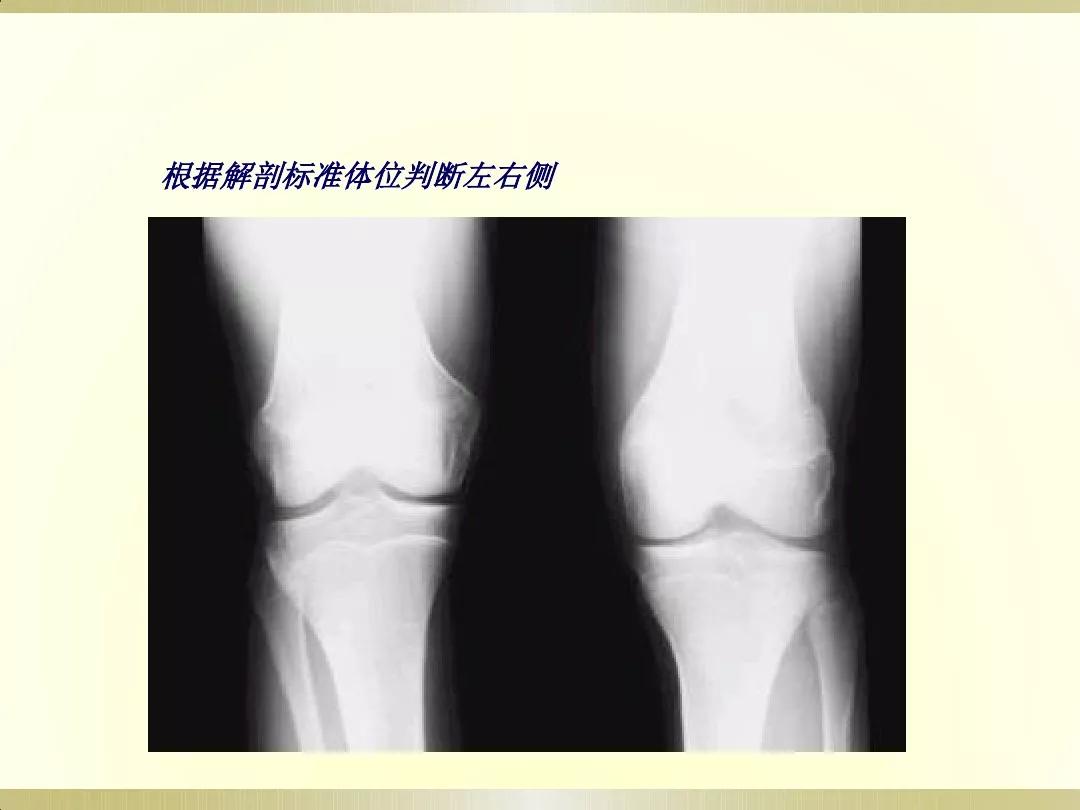

X线摄片就是通过让一种有能量的电磁波,即X射线透射过身体不同组织结构,在胶片上形成明暗或黑白对比不同的影像,被称为X线摄片。

医生可以通过X射线检查来识别各种组织,并根据阴影的形态和浓淡变化来分析其是否属于正常。这很像我们日常所说的拍照片,出来的图像是平面的。

检查部位:X线可以检查身体的许多部位。通常用于检查胸部(大致了解情况)、骨骼、肌肉或脏器,以及发现体内的气体,也可探查金属物体。